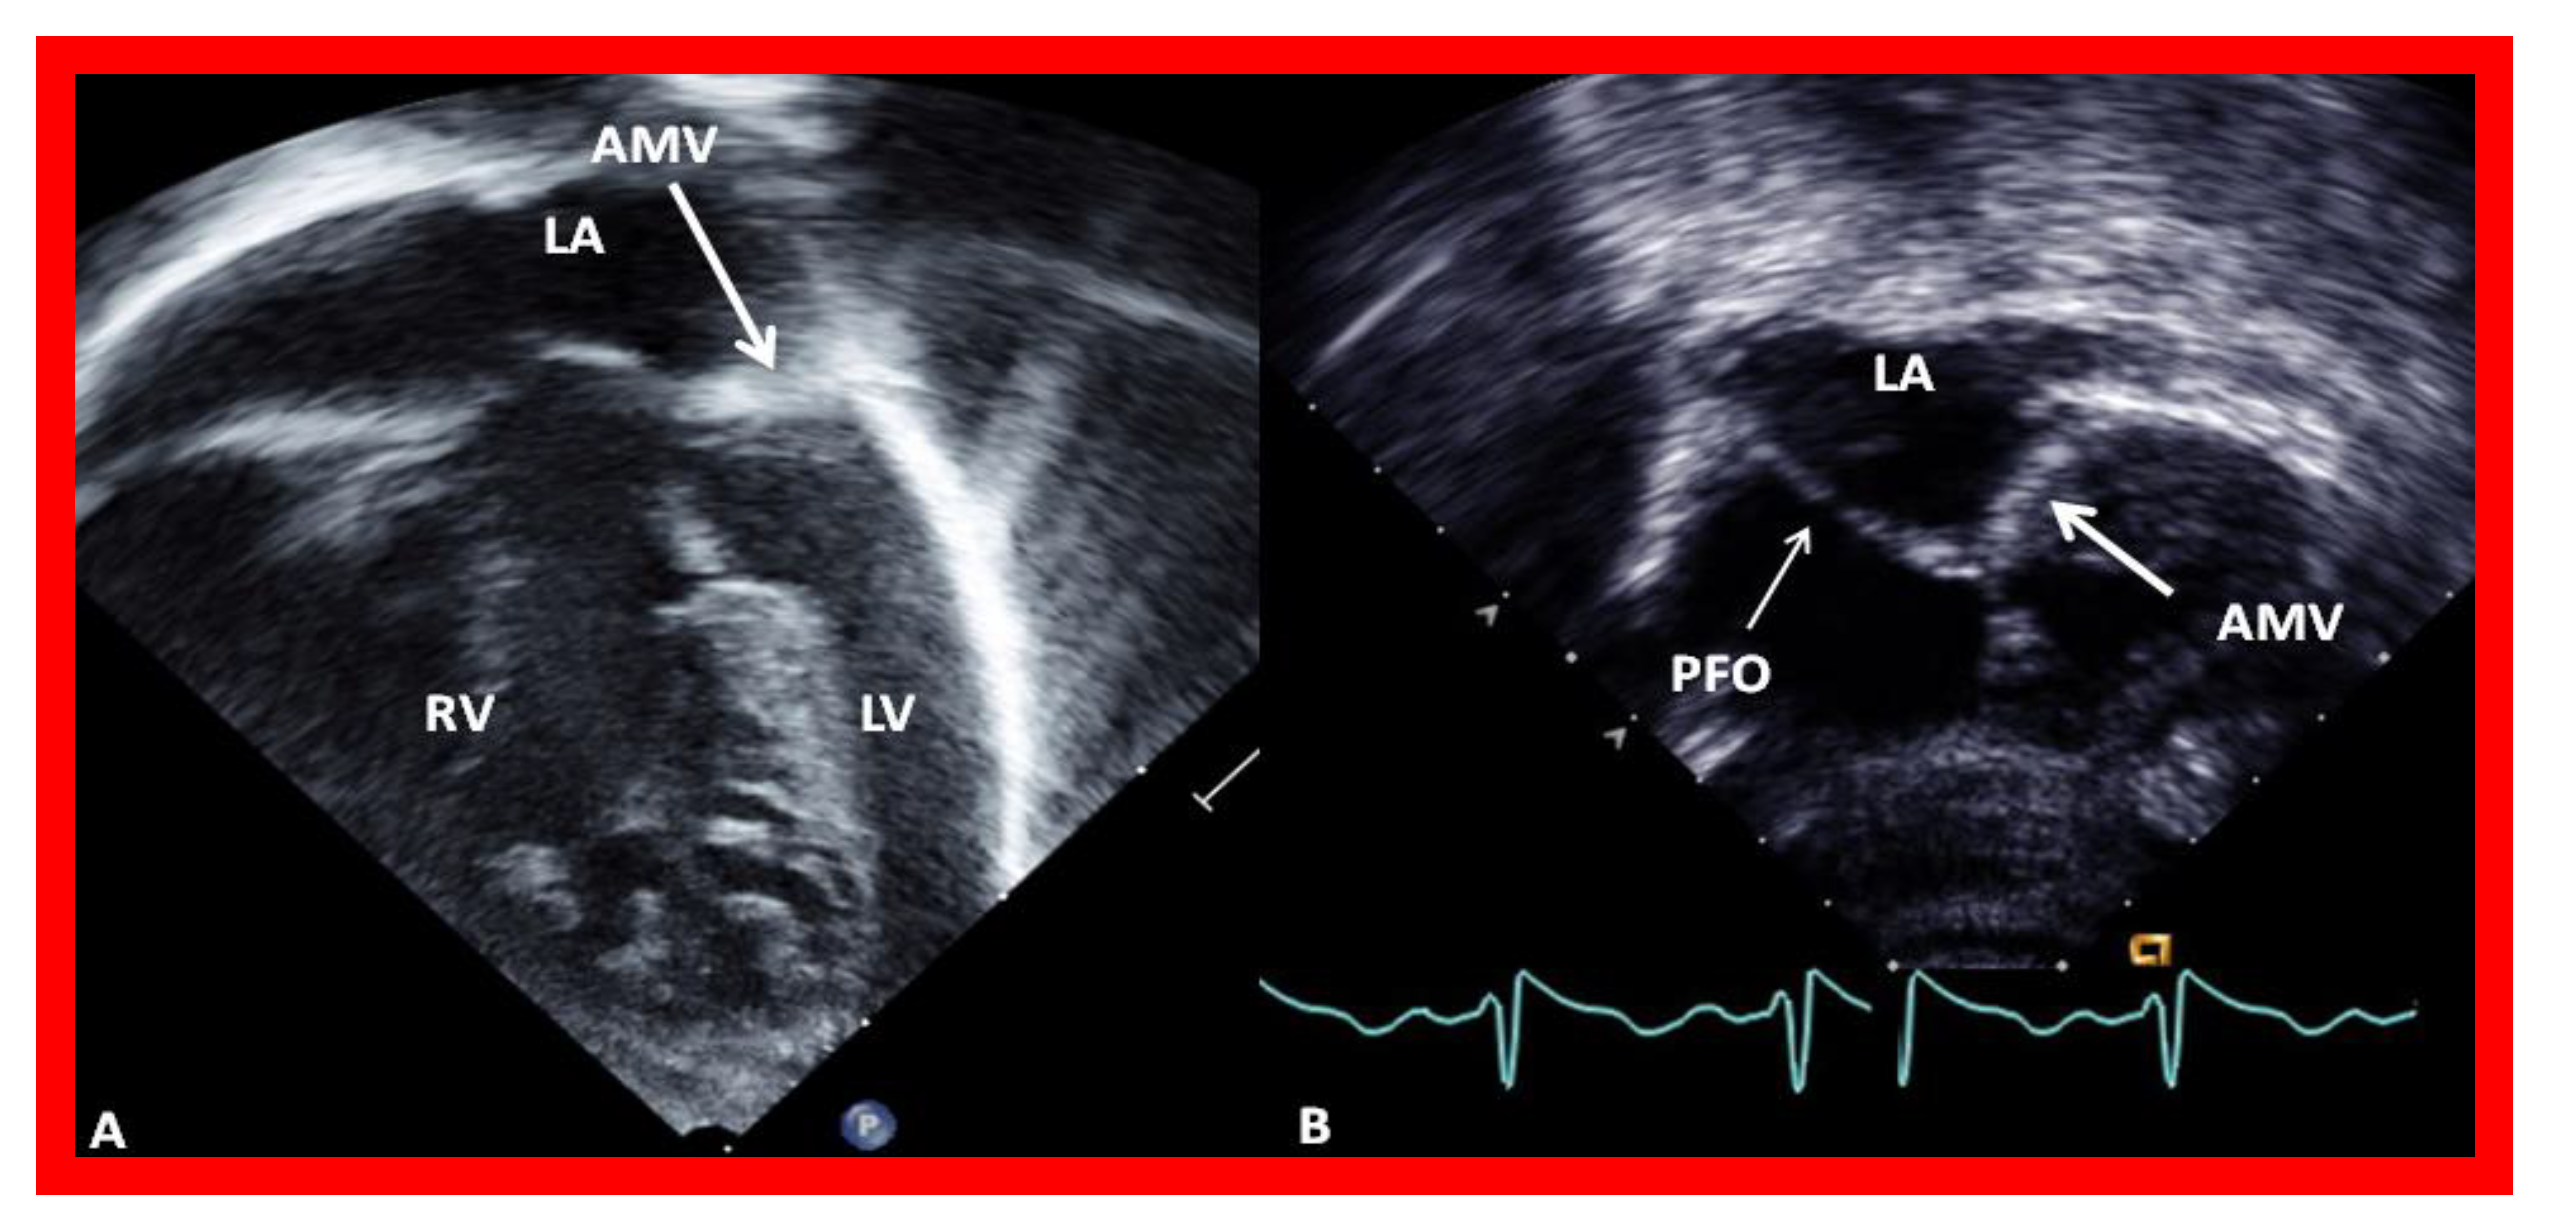

5.1. Restrictive Atrial Communication